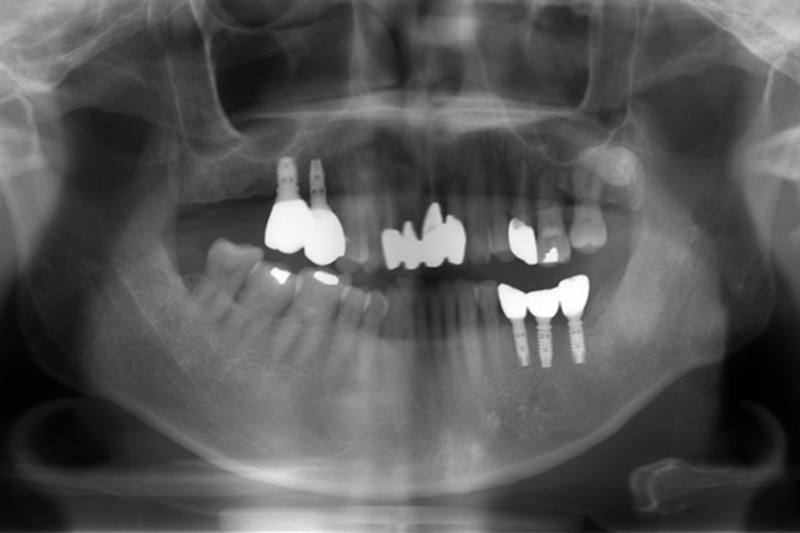

水雷射植牙重建 首頁 案例分享 植牙 水雷射植牙重建 水雷射植牙重建 案例A 治療前 治療後 聲明:本所療程皆由專業醫生評估後,依照個人口腔狀況進行治療。因每位患者個別狀況不同,術後狀況也不盡相同,需親來本所由醫生評估。